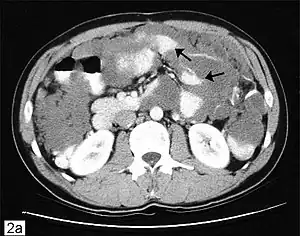

This disease is often discovered during surgery for other conditions, e.g., hernia repair, following which an experienced pathologist can confirm the diagnosis. Advanced stages may present as tumors palpable on the abdomen or distention of the belly ("jelly belly" is sometimes used as a slang term for the condition). Due to the rarity of this disease, it is important to obtain an accurate diagnosis so that appropriate treatment may be obtained from a Gastro intestinal cancer surgeon. Diagnostic tests may include CT scans, examination of tissue samples obtained through laparoscopy, and the evaluation of tumor markers. In most cases a colonoscopy is unsuitable as a diagnostic tool because in most cases appendix cancer invades the abdominal cavity but not the colon (however, spread inside the colon is occasionally reported). PET scans may be used to evaluate high-grade mucinous adenocarcinoma, but this test is not reliable for detecting low-grade tumors because those do not take up the dye which shows up on scans. New MRI procedures are being developed for disease monitoring, but standard MRIs are not typically used as a diagnostic tool. Diagnosis is confirmed through pathology.